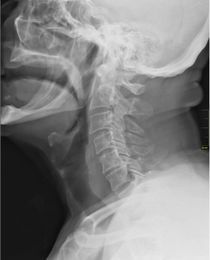

X-ray showing the throat, seen as a dark band to the front of the spine.  | |

الحلق (بالإنجليزية: Throat)، في علم التشريح، هو الجزء الداخلي من الرقبة، أمام الفقرات العنقية. ويحتوي على البلعوم (بالإنجليزية: pharynx) والحنجرة (بالإنجليزية: larynx).

ومن المميزات الرئيسية للحلق هو وجود لسان المزمار، وهو غضروف مرن يقوم بفصل المريء عن الرغامى، أو ما يعرف بالقصبة الهوائية، كي لا يدخل الطعام والشراب إلى الرئتين.

ويتكون الحلق من أوعية دموية، عضلات متنوعة، المرئ، الرغامى (القصبة الهوائية). وتعتبر عظمتا الرقبة والترقوة العظمتين الوحيدتين الموجودتين في حلق الإنسان.